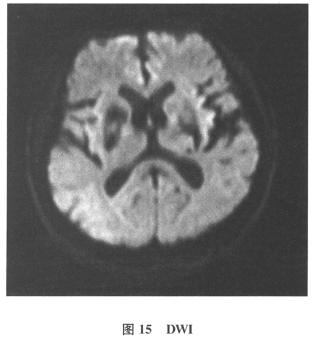

[多选题]患者男,61岁。因“发作性头晕2年,加重伴记忆力下降、走路不稳3月余”就诊。查体:BP140/70mmHg;意识清楚,构音障碍,近期记忆力及远期记忆力